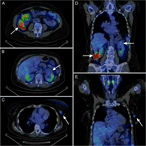

Successful treatment of three synchronous primary malignant tumours—reflection on surgical, pathological and oncological aspects and decision making

Emese Irma Ágoston and others

Journal of Surgical Case Reports, Volume 2018, Issue 4, April 2018, rjy041, https://doi.org/10.1093/jscr/rjy041